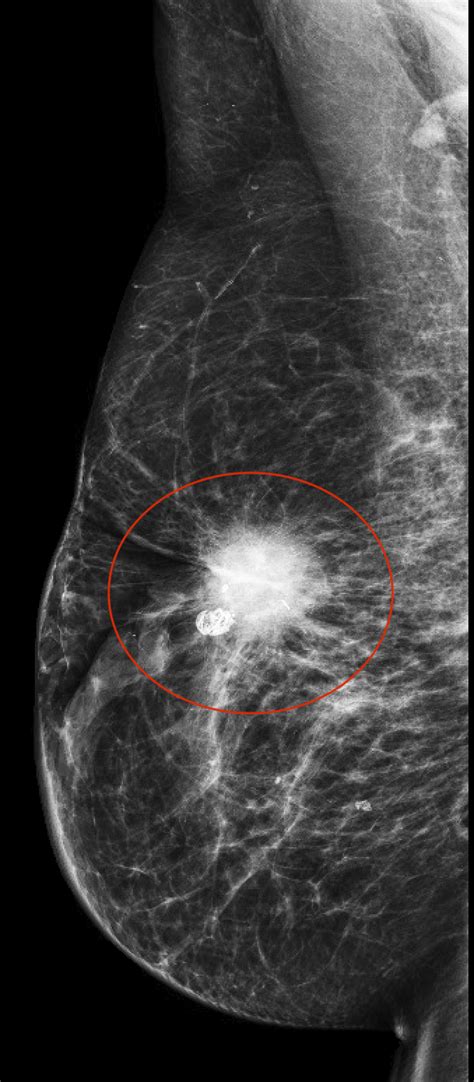

• Mammogram: An X-ray of the breast to detect any masses or abnormalities.